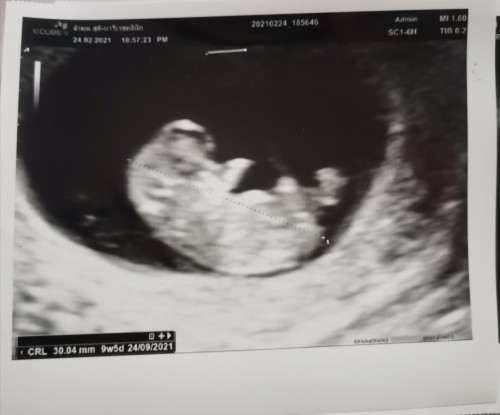

9w5dจร้าเห็นน้องแล้วจร้าแม่